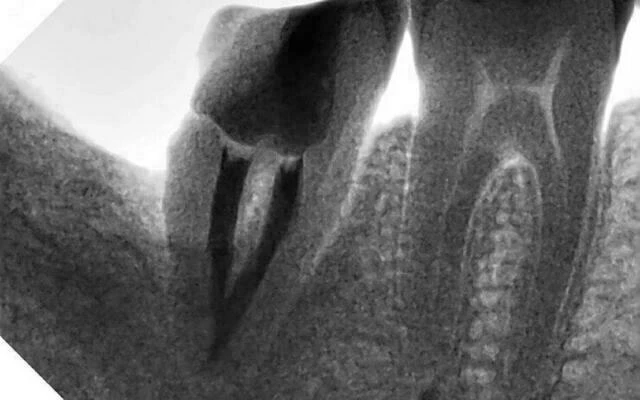

1. Bệnh nhân nam 39 tuổi tới khám vì lý do cắn vỡ một phần răng 47 có nhu cầu làm chụp răng. Bệnh nhân có tiền sử nhổ răng 48 mọc lệch gây sâu phía xa răng 47. Răng 47 đã được điều trị tủy cách đây gần 1 năm ở phòng khám khác.

Khám thấy răng 47 vỡ lớn phía xa, còn một phần chất hàn cũ mặt nhai. Lợi xung quanh bình thường. Phía xa có túi lợi sâu (không đo). Gõ dọc gõ ngang không đau.